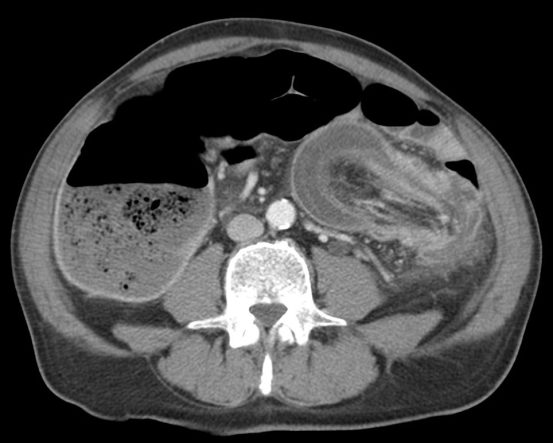

- Masa con baja densidad intraluminal + patrón de burbujas de aire moteado ( patrón característico).

- Edema de pared y engrosamiento de mucosa.

- Obstrucción intestinal: cambios de calibre y dilatación de asas pre estenosis. El CT puede determinar la causa, localización y grado de obstrucción intstinal.

- El CT puede ayudar a distinguir entre un bezoar y particulas de comida. Los bezoares son redondos u ovoides, flotan en la superficie de agua/aire rodeados del contenido gástrico y que además muestran menor densidad que las partículas de comida. Los bezoares grandes tienden a rellenar todo el lumen y muestran burbujas distribuidas en el intersticio de la masa. Sin embargo, en ocasiones puede ser dificil difrenciar un bezoar de un cantidad considerable de comida retenida o de las heces si se localizan en el colon. Un hallazgo que puede ayudarnos, es identificar que dicha masa esta produciendo una obstrucción.

- La ventana estándar abdominal de (level, 40 H; width, 350 H) puede hacer muy dificil el diagnóstico de bezoar. Es recomendable bajar el Nivel/Level de la ventana hasta los L -1oo H o jugar con dichos niveles hasta identificar mejor las características del bezoar.